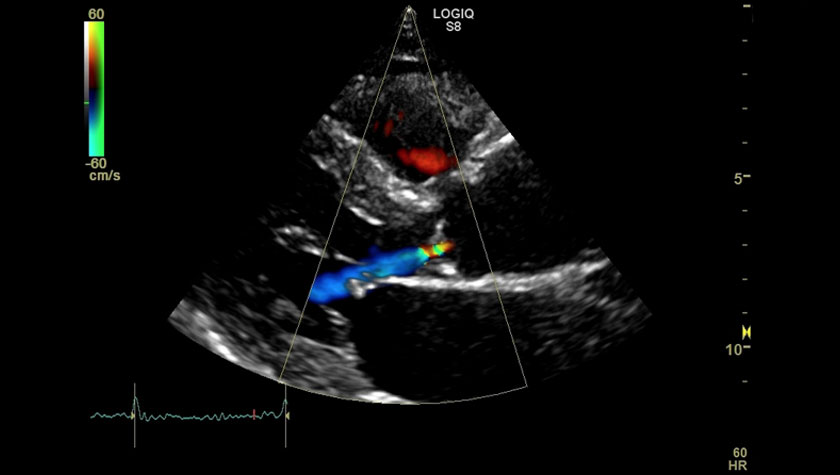

Аортальный клапан, режим цветного доплера, датчик M%S-D